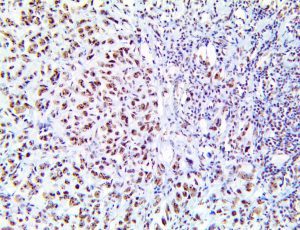

The first cytokines released are interleukin 1β (IL-1β) and tumor necrosis factor-α (TNF-α), which attract a variety of circulating white blood cells (WBCs) to the infection site, including neutrophils, monocytes, macrophages, and natural killer (NK) cells. This response, along with the antipathogenic chemicals released by these cells (i.e., complement), comprise the innate immune response. These cells directly attack the invading pathogen and also release additional cytokines, chief among them interleukin-1 and 6 (IL-6). IL-6 is essential for invoking the adaptive immune response, which calls T-cells, B-cells, and T helper (Th) cells to the infection site. IL-6 also stimulates further recruitment, proliferation and activation of macrophages.

It is the ICU physician who is most likely to witness one of the deadliest manifestations of the abnormal immunological response, the cytokine storm syndrome (CSS). This response is also referred to by some as the cytokine release syndrome (CRS). CSS is characterized by continuous activation and expansion of macrophage and lymphocyte populations, which secrete large amounts of cytokines, causing the cytokine storm. This massive cytokine release is akin to hemophagocytic lymphohistiocytosis (HLH) disease, a syndrome characterized by initial unchecked and persistent activation of cytotoxic T lymphocytes and NK cells.

This activation induces inflammatory monocytes to highly express IL-6, starting a localized and then systemic cascade effect that results in hyperproduction of IL-6, which accelerates the inflammatory process. Because IL-6 also increases vascular permeability, excessive levels cause blood vessels to become very leaky. This, along with clotting factors released from vascular endothelial cells, stimulates the coagulation cascade, resulting in microthrombosis (tiny clots), which leads to ischemia and tissue death of the kidney, intestines, heart, liver, brain and extremities.